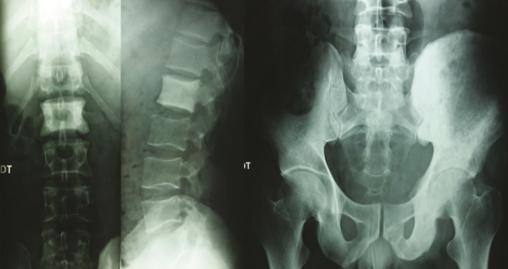

Les radiographies standards mettent en évidence une vertèbre ivoire L1 ainsi qu’une ostéocondensation de l’os iliaque gauche (fig. 1 ). Le scanner thoraco-abdomino-pelvien montre une atteinte osseuse mixte de l’aile iliaque gauche (fig. 2 ), un envahissement des parties molles (avec augmentation des volumes des muscles fessiers et du psoas [fig. 3 ] expliquant la sciatalgie), une néphromégalie unilatérale, une splénomégalie nodulaire et de multiples adénopathies abdomino-pelviennes et thoraciques.

Les radiographies standards mettent en évidence une vertèbre ivoire L1 ainsi qu’une ostéocondensation de l’os iliaque gauche (